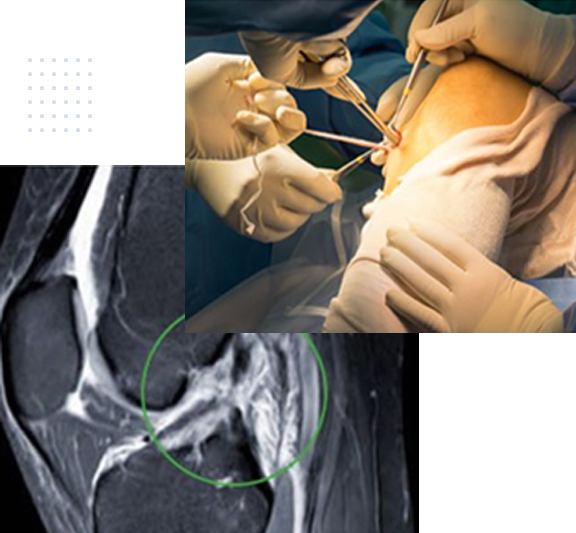

In der Ortho Clinic behandeln Dr. Tim Briem und Dr. Igor Killer Casparis das gesamte Spektrum von unfallchirurgischen und orthopädischen Erkrankungen rund um das Knie. Neben einer ausführlichen konservativen Behandlung wird auch ein sehr breites operatives Spektrum abgedeckt. Neben arthroskopischen Operationen gehören offene chirurgische Eingriffe zu unserer Expertise. Unfälle mit z.B. Verletzungen des Kreuzbandes oder Meniskusverletzungen werden ebenso standardisiert und häufig durchgeführt wie Gelenkersatz-Operationen bei fortgeschrittener Arthrose.

Knorpelchirurgie am Knie

Die Behandlung von Knorpelschäden im Knie, bzw. allgemein stellt eine große Herausforderung in der Orthopädie dar.

Knorpelzellen haben einen sehr langsamen Stoffwechsel. Darüber hinaus zeigen sie im Erwachsenen-Alter nahezu keine Tendenz mehr zur Selbstheilung. Daher kommt einer möglichst frühzeitigen und konsequenten Behandlung eines Knorpelschadens grosse Bedeutung zu.

Verletzungen des vorderen Kreuzbandes

Das vordere Kreuzband (VKB) spielt eine entscheidende Rolle bei der Stabilität des Kniegelenks.

Verletzungen dieses Bandes sind bei Aktivitäten mit plötzlichen Richtungswechseln oder abrupten Stopps häufiger. Ein Riss des vorderen Kreuzbandes können zu erheblichen funktionellen Beeinträchtigungen und langfristigen Komplikationen führen